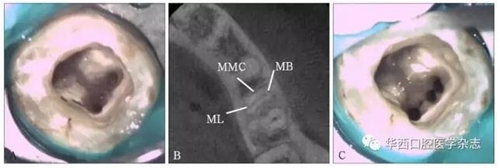

左:直視下定位MMC(箭頭所示);右:完全預(yù)備后的MMC。

圖 1下頜第一磨牙開髓后直視下探查近中根 顯微鏡 ×16

A:CBCT分析前未探查到MMC 顯微鏡 ×16;

B:CBCT分析顯示近中根三根管;

C:完全預(yù)備后的MMC 顯微鏡 ×16。

圖3 CBCT分析后應(yīng)用顯微超聲技術(shù)輔助探查下頜第一磨牙近中根